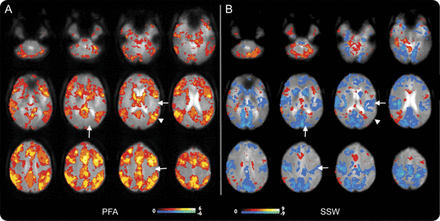

在所有患者6 PFA,皮质大胆的改变几乎完全是积极的信号。外显率的分布地图显示激活(图2一个;个案如图e 1上首页®网站www.首页neurology.org)。PFA-related大胆的增加主要影响广泛的额叶皮质“协会”地区,顶叶枕叶和颞叶,但似乎并没有意识到涉及初级皮层。

结合阈值SPM PFA的“外显率地图”(A)和(B)西南偏南约显示大脑皮层和皮层下的整体模式的激活和解除激活这些癫痫样的事件。颜色代表对象的数量规模与显著激活体素(黄色高于阈值的像素点为所有6科目PFA和9 f)。增加在大胆的信号显示在暖色和冷色的减少。没有大胆的反应主要在PFA皮质;初级运动、视觉和听觉皮层(箭头)没有激活或不激活体素,而所有这些领域显示减少大胆在f(同样的箭头在B)。在联合皮质(例如,箭头在顶叶皮层)强烈激活在量和没有大胆的在量的变化。这是真的协会地区除了一些地区的额叶皮质显示量的失活。皮层下结构,如脑干和尾状,显示激活量在PFA和失活。尽管个人更多的变化结果与量覆盖所有情况下导致这种识别的模式。大胆=血氧等级相关;PFA =阵发性快速活动; SPM = Statistical Parametric Mapping; SSW = slow spike and wave.

在5 6 PFA的数据集,有大胆的信号增加丘脑。大胆的信号增加尾状核和基底神经节也观察到在5 6例。单边模式时或者有单侧性的强调,PFA和大胆的信号变化的偏侧性与解剖病变,和最大的一侧丘脑参与与最大的一侧皮质的变化。

脑干显示增加大胆信号subcollicular水平与PFA的4 6例。小脑激活被认为在大多数主题(5 6)。

缓慢的上升和波。

量排放记录9例。他们与正面和负面的皮质大胆的混合信号的变化(图2、e 1和飞行)。

不像PFA,皮质是西南偏南约模式变量(图飞行)。的一部分,这可能是由于有限的数据量(患者9、10、13)。患者6,7,8弱难以解释的激活。患者1、2和5有强烈激活外显率最佳解释的引用映射(图2)。这表明失活往往是在初级皮质(电动机、视觉和听觉)和中线顶叶皮层。有分散在其他领域积极激活皮层,特别是额叶皮层的某些地区。

大胆的信号变化4例患者出现丘脑在场。这些都是双边积极2(病人1和5),双边-在一个病人(6),和积极的一面和消极变化在另一个病人(2)。

有4例患者出现大胆的尾状核的活动减少,这是外显率的地图(图2)。脑干显示大胆的信号变化subcollicular水平4例(2增加和减少2)。

我们的研究的主要发现是PFA和f (LGS)的2定义电记录的特性有独特和明显不同的大脑皮层和皮层下大胆的信号变化模式。PFA显示了一个独特的、分散和一致的“激活”,大脑的许多地方,特别是在协会皮层(图2)。

PFA显示激活在广泛领域的皮层,但似乎备用主皮质。PFA显示增加大胆信号的皮层下结构包括丘脑、基底神经节,和脑干,所有已知的“联合皮层有广泛的联系。“这观察激活在许多领域与协会有关皮层和皮层下系统,但不包括初级皮层,导致我们称之为网络激活,我们看到在PFA”扩散协会网络激活”(DANA)。此外,在大多数情况下,不同的左/右或前/后头皮排放的重点体现在前/后招聘比例左/右或分散的网络。

然后生成一个比PFA显然不同模式的大胆的信号改变。量模式的失活后扣带和楔前叶也不同于之前报道的变化在典型的飙升和专家组的波。13,- - - - - -,16,29日,- - - - - -,31日在西南偏南约LGS更不规则和不对称的,经常有节奏的、持续的比典型3-Hz棘波放电。虽然整体脑电图出现的量给的印象均匀广泛的广义皮质活动,不一致和不完整的激活在我们的情况下可能反映了这些著名的不规则脑电图的发现。不同于典型的广义飙升和西南偏南约波(GSW)15,27,29日在几个方面,包括失活主要的皮质,模式的可变性,丘脑激活不一致,偶尔积极激活在尾状,基底神经节。还需要进一步的研究来探索这些功能的可靠性。